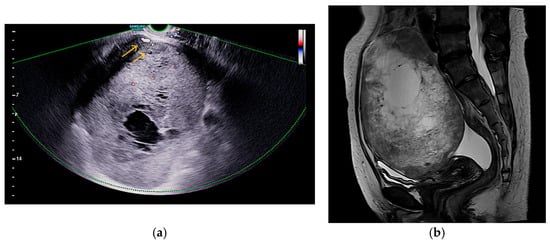

A 48-year-old nulliparous woman presented with a palpable pelvic mass and a three-month history of progressive abdominal discomfort. She had no notable medical or surgical history and no known family history of malignancy. Transvaginal ultrasound revealed a 16 cm multilocular cystic mass in the left adnexa with irregular echogenic solid components and papillary projections. Gynecologic sonography with Doppler imaging demonstrated internal vascularity within the solid areas, raising suspicion for malignancy (Figure 1a). No ascites or peritoneal implants were observed, and the contralateral adnexa appeared unremarkable. Pelvic MRI revealed that the mass exhibited uniformly low signal intensity on T1-weighted images, while T2-weighted sequences demonstrated a combination of low and high signal areas, indicative of a lesion with both cystic and solid components. (Figure 1b). Chest CT revealed no evidence of metastatic disease, and PET-CT showed only mild FDG uptake in a left para-aortic lymph node. Both upper and lower endoscopies were unremarkable. Serum tumor markers showed elevated CA-125 (68.5 U/mL), while HE4, CEA, CA19-9, and AFP were within normal limits. The ROMA score was low at 9.04% (premenopausal low-risk threshold: <11.4%). Exploratory laparotomy revealed a ruptured left ovarian mass measuring 16.0 cm × 12.0 cm × 9.0 cm, densely adherent to the sigmoid colon, rectum, and parietal pelvic peritoneum, without gross peritoneal implants or enlarged lymph nodes. The patient underwent total abdominal hysterectomy with bilateral salpingo-oophorectomy, pelvic and para-aortic lymphadenectomy, total omentectomy, and meticulous adhesiolysis.

Figure 1.

Imaging features of the pelvic mass: (a) Doppler ultrasound shows internal vascularity in solid areas without ascites or peritoneal implants, as indicated by the arrows; (b) Sagittal T2-weighted MRI shows mixed signal intensity, indicating cystic and solid components.